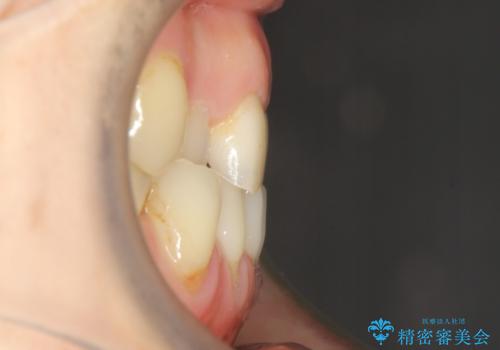

反対咬合や欠損を治療したい インビザライン矯正とオールセラミックブリッジ

- 虫歯治療がうまく進まないとのことで来院された患者様です。

虫歯治療や欠損補綴治療も必要でしたが、前歯が反対咬合であったので、セラミッククラウンやブリッジによる治療と並行して矯正治療を提案しました。

仕事柄海外出張が多いとのことで、虫歯治療後にインビザラインにて矯正治療を行うこととしました。